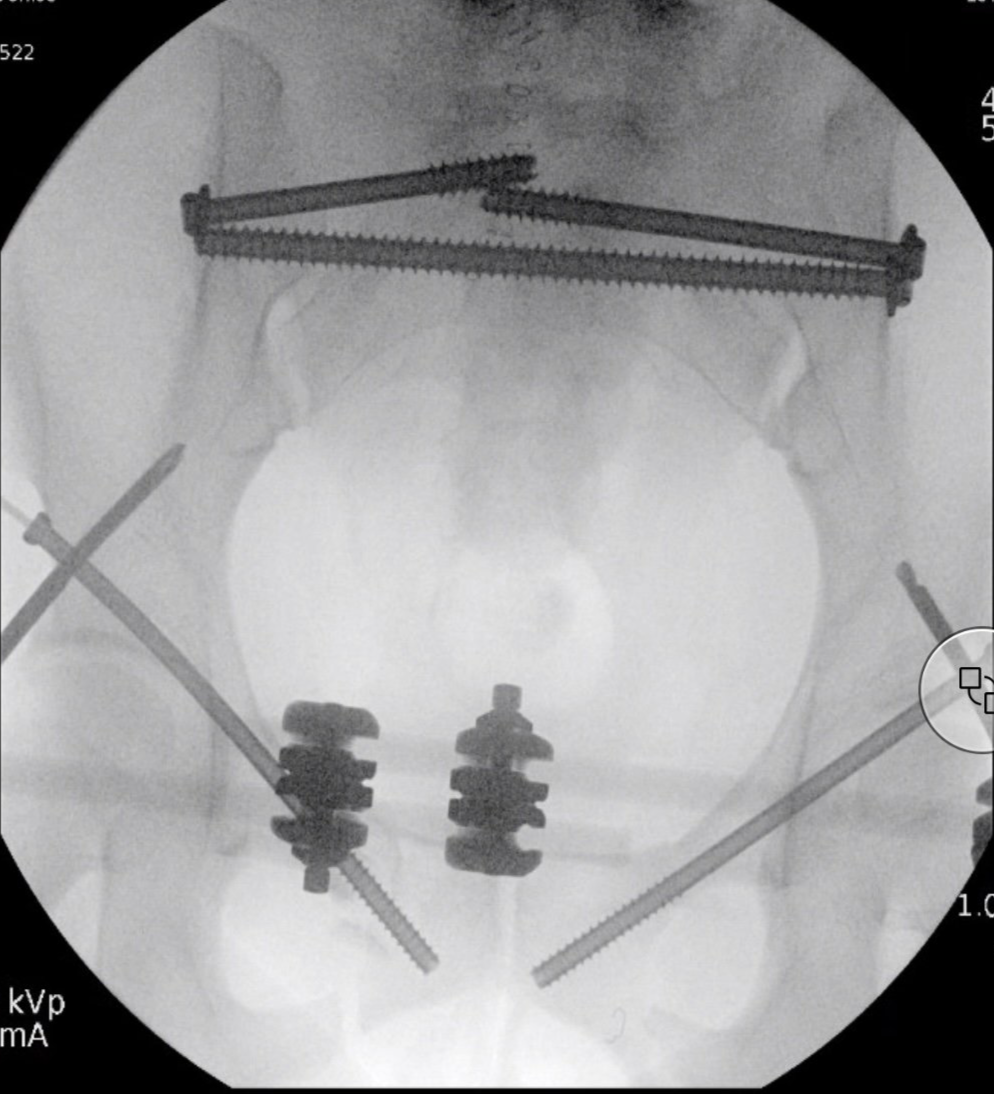

Dr Godwin specialises in the management of complex pelvic trauma, offering cutting-edge surgical solutions using the latest techniques and technology. One of the cornerstone tools in our pelvic trauma repertoire is the Starr Pelvic Reduction Frame, a system designed to enable accurate, minimally invasive reduction of pelvic ring and acetabular fractures.

The Starr Frame is an external reduction device used during surgery to precisely manipulate and stabilise fractured pelvic bones. It allows for controlled, multiplanar reduction with minimal soft tissue disruption. When combined with fluoroscopy and percutaneous fixation techniques, it offers a powerful method for managing: